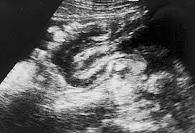

- La ecografía abdominal o diagnóstico por imágenes. Tomando las imágenes del abdomen con ultrasonidos, rayos X o la tomografía computarizada (TC) puede mostrar una obstrucción intestinal causada por invaginación intestinal. la proyección de imagen abdominal también puede mostrar si el intestino se rompió (perforado).